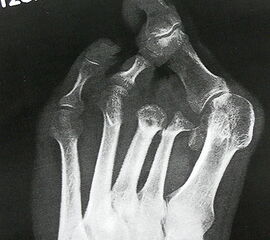

Exartikulationen im Großzehengrundgelenk bedingen bei Neuropathie häufig Druckulze­rationen am Metatarsalekopf (Abb. 6, 7). Wenn vertretbar, wird die Basis des Grundglieds mit den Sehnensansätzen erhalten, um chronische Druckprobleme zu vermeiden (Abb. 8). Im Falle einer Exartikulation ist dem Druck unter dem Metatarsale-I-Kopf große Aufmerksamkeit zu widmen. Durch eine Entfernung der Sesambeine und Abtragen von plantaren knöchernen Prominenzen kann die Auflagefläche vergrößert und damit der Druck reduziert werden. Postoperativ muss der Mittelfuß durch Einlagen in seinem Gewölbe breitflächig abgestützt werden (Abb. 9). Ansonsten resultiert ein Plattfuß mit Pronation und Abduktion.

Wegen des Risikos einer Ulzeration am Metatarsalekopf (Abb. 14) sollte die Exartikulation im Grundgelenk vermieden werden. Günstiger ist es, falls möglich, einen kurzen Grundglied­stumpf als Platzhalter zu belassen (Abb. 15). Wenn Zehen in eine Lücke zu kippen drohen, kann die mit einem Platzhalter verhindert werden (Abb. 16, 17)